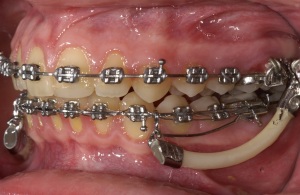

festsitzende Bisslagekorrektur (Jasper-Jumper)